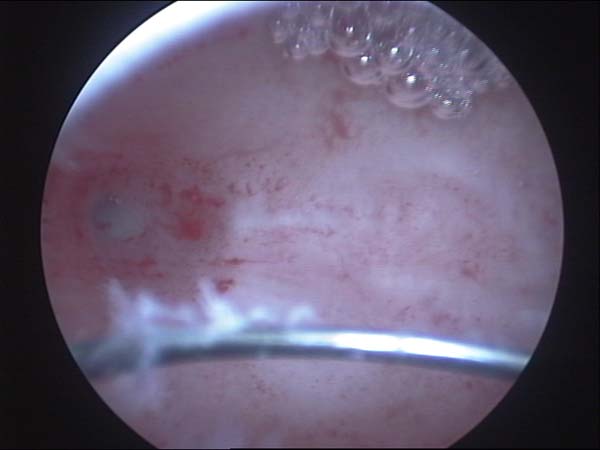

- Hysteroscopy Video clips

- Hysteroscopy Photos

Hysteroscopy Pictures | Dr N Layyous